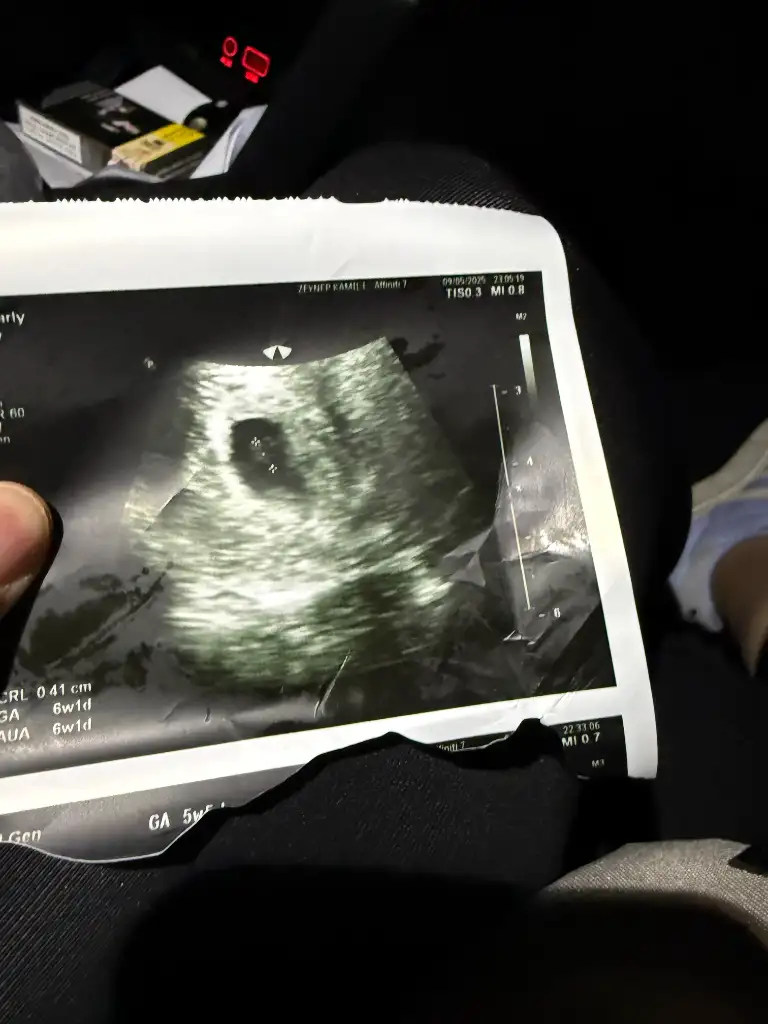

Merhaba, benim bebeğimde 10+4 bir tahmin yapılabiliyor mu acaba 🥰